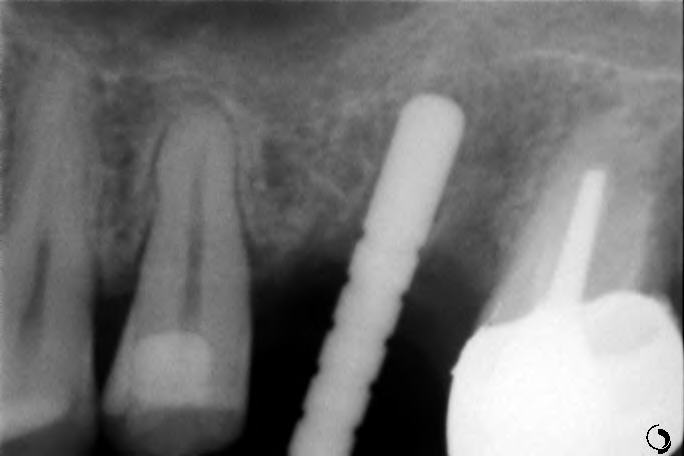

Le sinus lift (accès par voie latérale) : lorsqu’il manque de l’os en arrière du maxillaire supérieur, on accède au sinus par une paroi latérale et on le comble avec nos matériaux. Cela augmente la hauteur osseuse disponible.

Le push-back (apport par voie crestale) : cette méthode permet d’apporter de l’os par le trou de forage lors de la pose de l’implant.